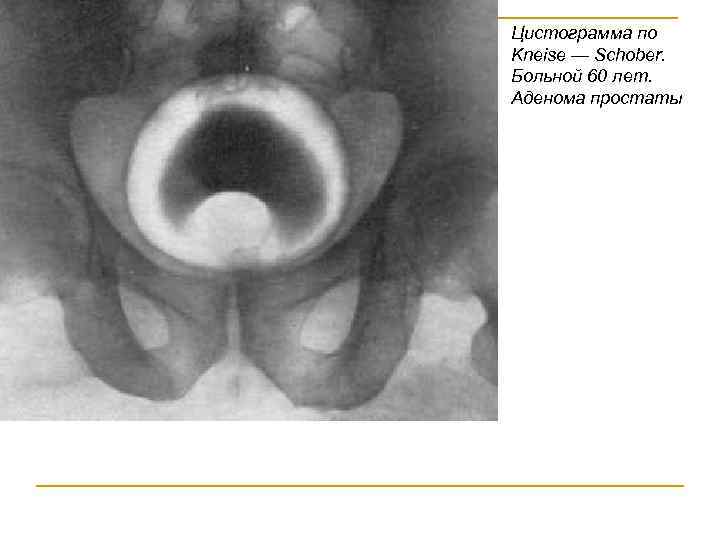

Цистограмма по Kneise — Schober. Больной 60 лет. Аденома простаты